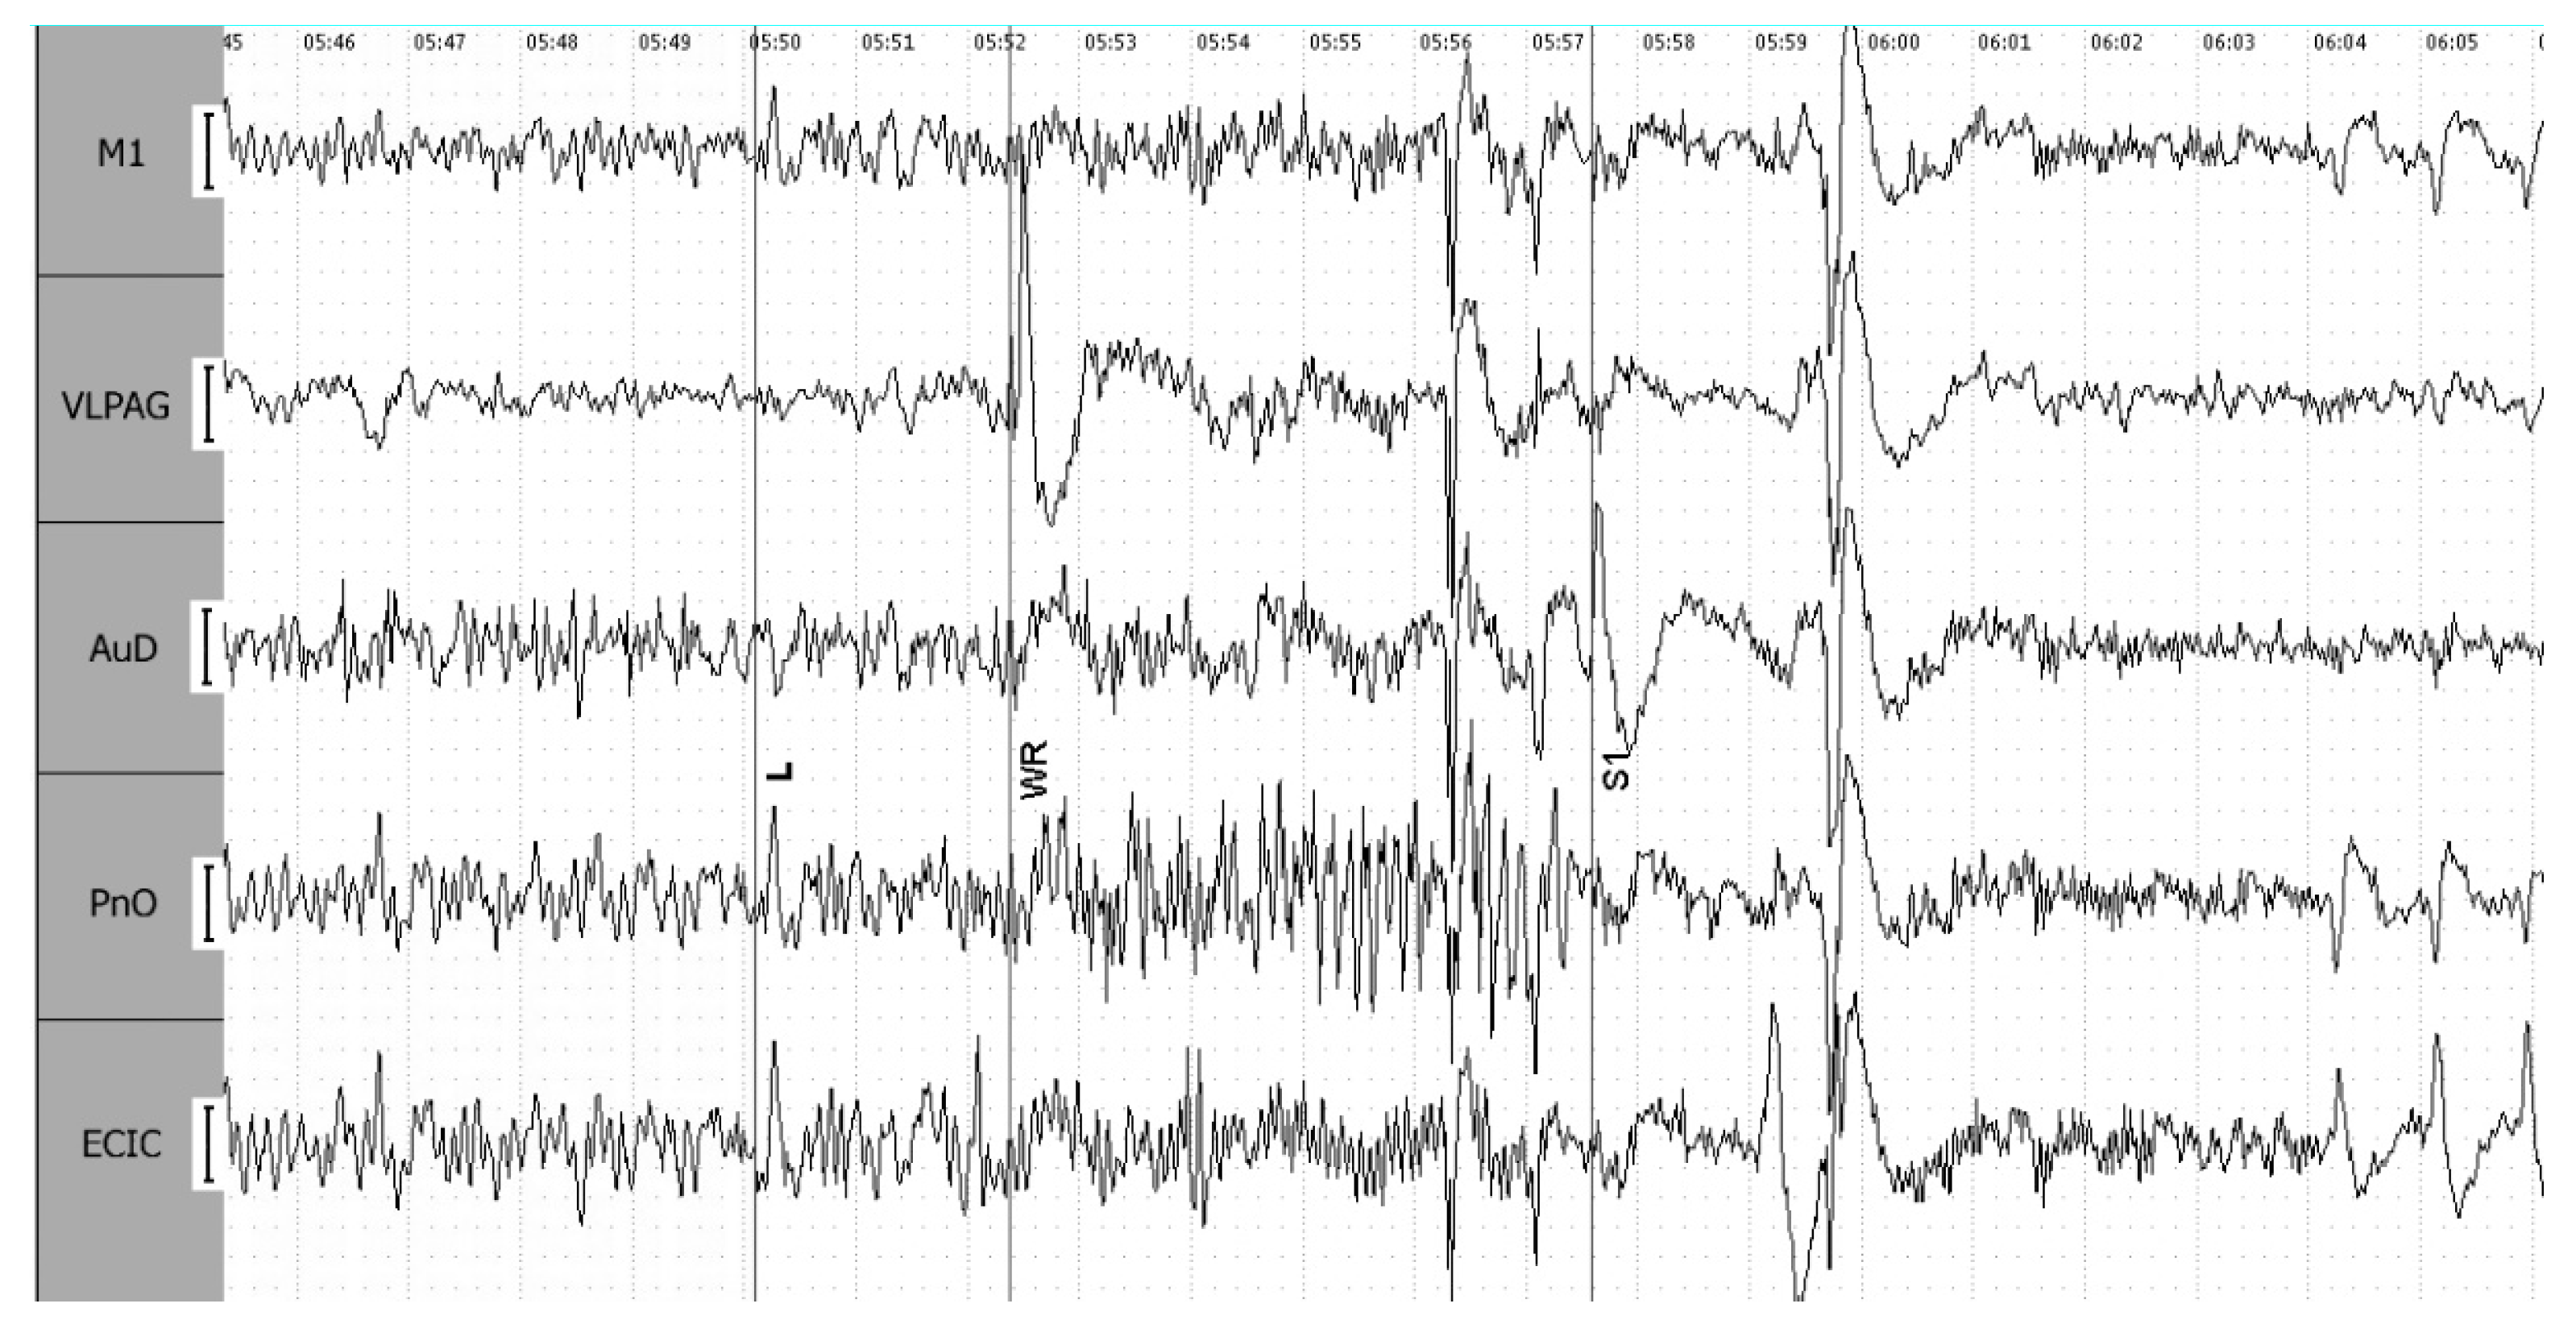

3.1. Electroencephalographic Recordings

3.1.2. Phases of 4-Point Seizures